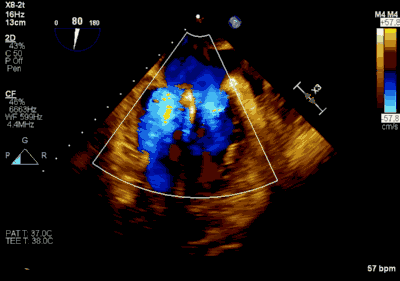

▲ 术前超声检查显示重度二尖瓣反流